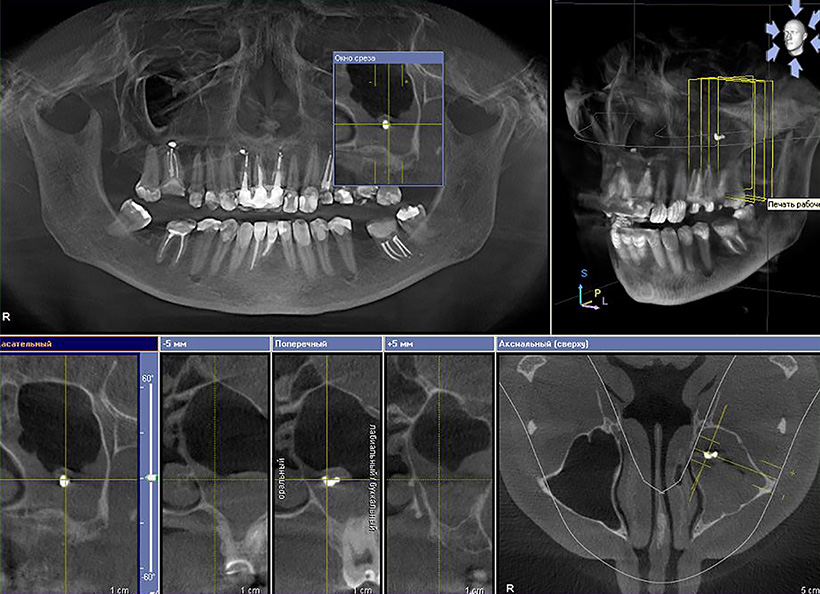

3D-томограмма — это цифровое трёхмерное изображение зубочелюстной системы, получаемое путем рентгенодиагностического исследования на дентальном компьютерном 3D-томографе.

Процедура диагностики проста и надёжна. Зона облучения ограничена конусообразным рентгеновским лучом. Луч проходит только через очень маленький участок диагностируемой области пациента, в результате чего получается трёхмерное изображение невероятно высокого разрешения, при минимальной дозе рентгеновского облучения. Компьютерная программа воспроизводит трёхмерное цифровое изображение в течение 1–2 минут, при этом врач имеет возможность просмотреть более детально снимок по трем осям, послойно или с необходимым интервалом.

Широкий спектр применения этого инновационного оборудования обусловлен не только чистотой и высоким качеством изображения зубного ряда и не прорезавшихся зубов, но и отображением важнейших деталей, включая строения корневых каналов, заболевания пародонта, дефекты альвеолярной кости.

Диагностические возможности томографа неоценимы при травмах зубочелюстной системы и зубов, аномалиях развития зубов и челюстей, хронических очаговых инфекциях лицевого черепа (когда сложно установить причину болевых ощущений), в имплантологии, сложном удалении и протезировании зубов.